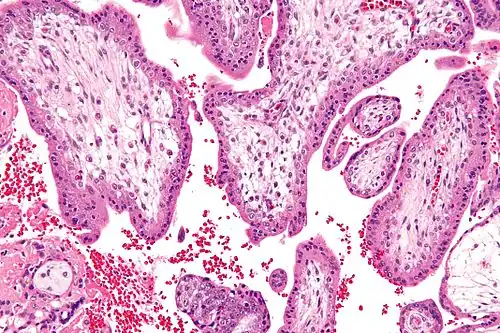

![]() Micrograph showing chorionic villi—the tissue that is collected in CVS. H&E stain. | |

Chorionic villus sampling (CVS), sometimes called "chorionic villous sampling" (as "villous" is the adjectival form of the word "villus"),[1] is a form of prenatal diagnosis done to determine chromosomal or genetic disorders in the fetus. It entails sampling of the chorionic villus (placental tissue) and testing it for chromosomal abnormalities, usually with FISH or PCR. CVS usually takes place at 10–12 weeks' gestation, earlier than amniocentesis or percutaneous umbilical cord blood sampling. It is the preferred technique before 15 weeks.[2]